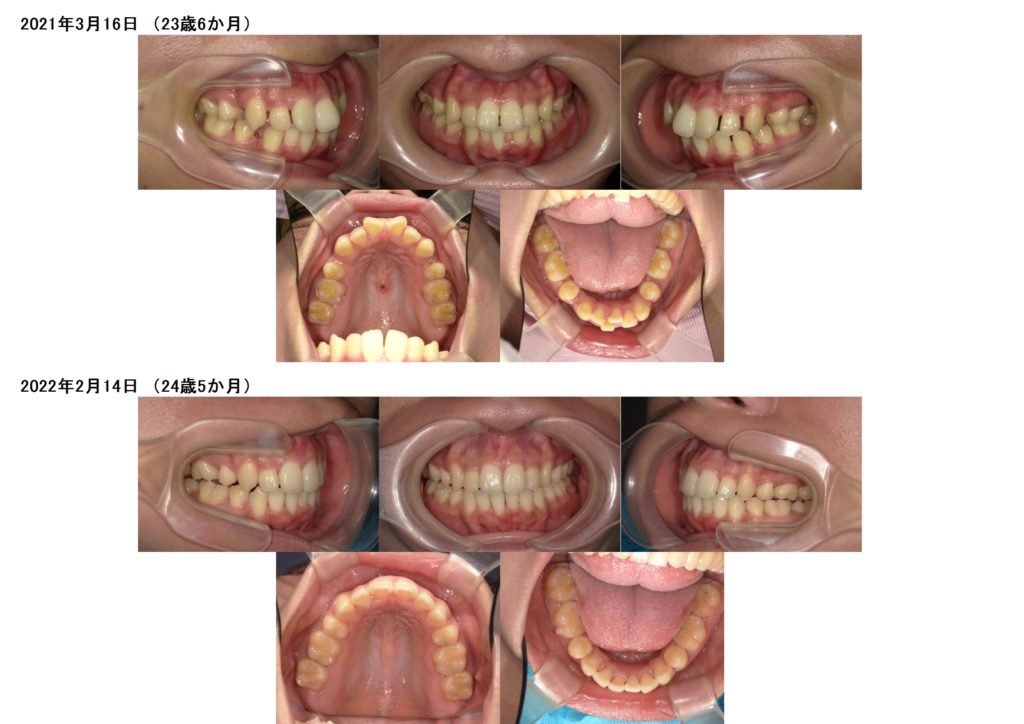

今回はマウスピースでの矯正治療をされた患者さまの治療例です。

上下4番目の歯を抜歯して治療をしました。

少しずつですが確実に前歯も引っ込み、ガタガタ歯並びも治っていますよね。

5カ月ぐらいで噛み合わせも安定しキッチリと並びました。

治療前、治療後の口腔内写真です。

お口元も引っ込み、ガタガタ歯並びも治りました。

横顔もとっても変わりましたよ☆